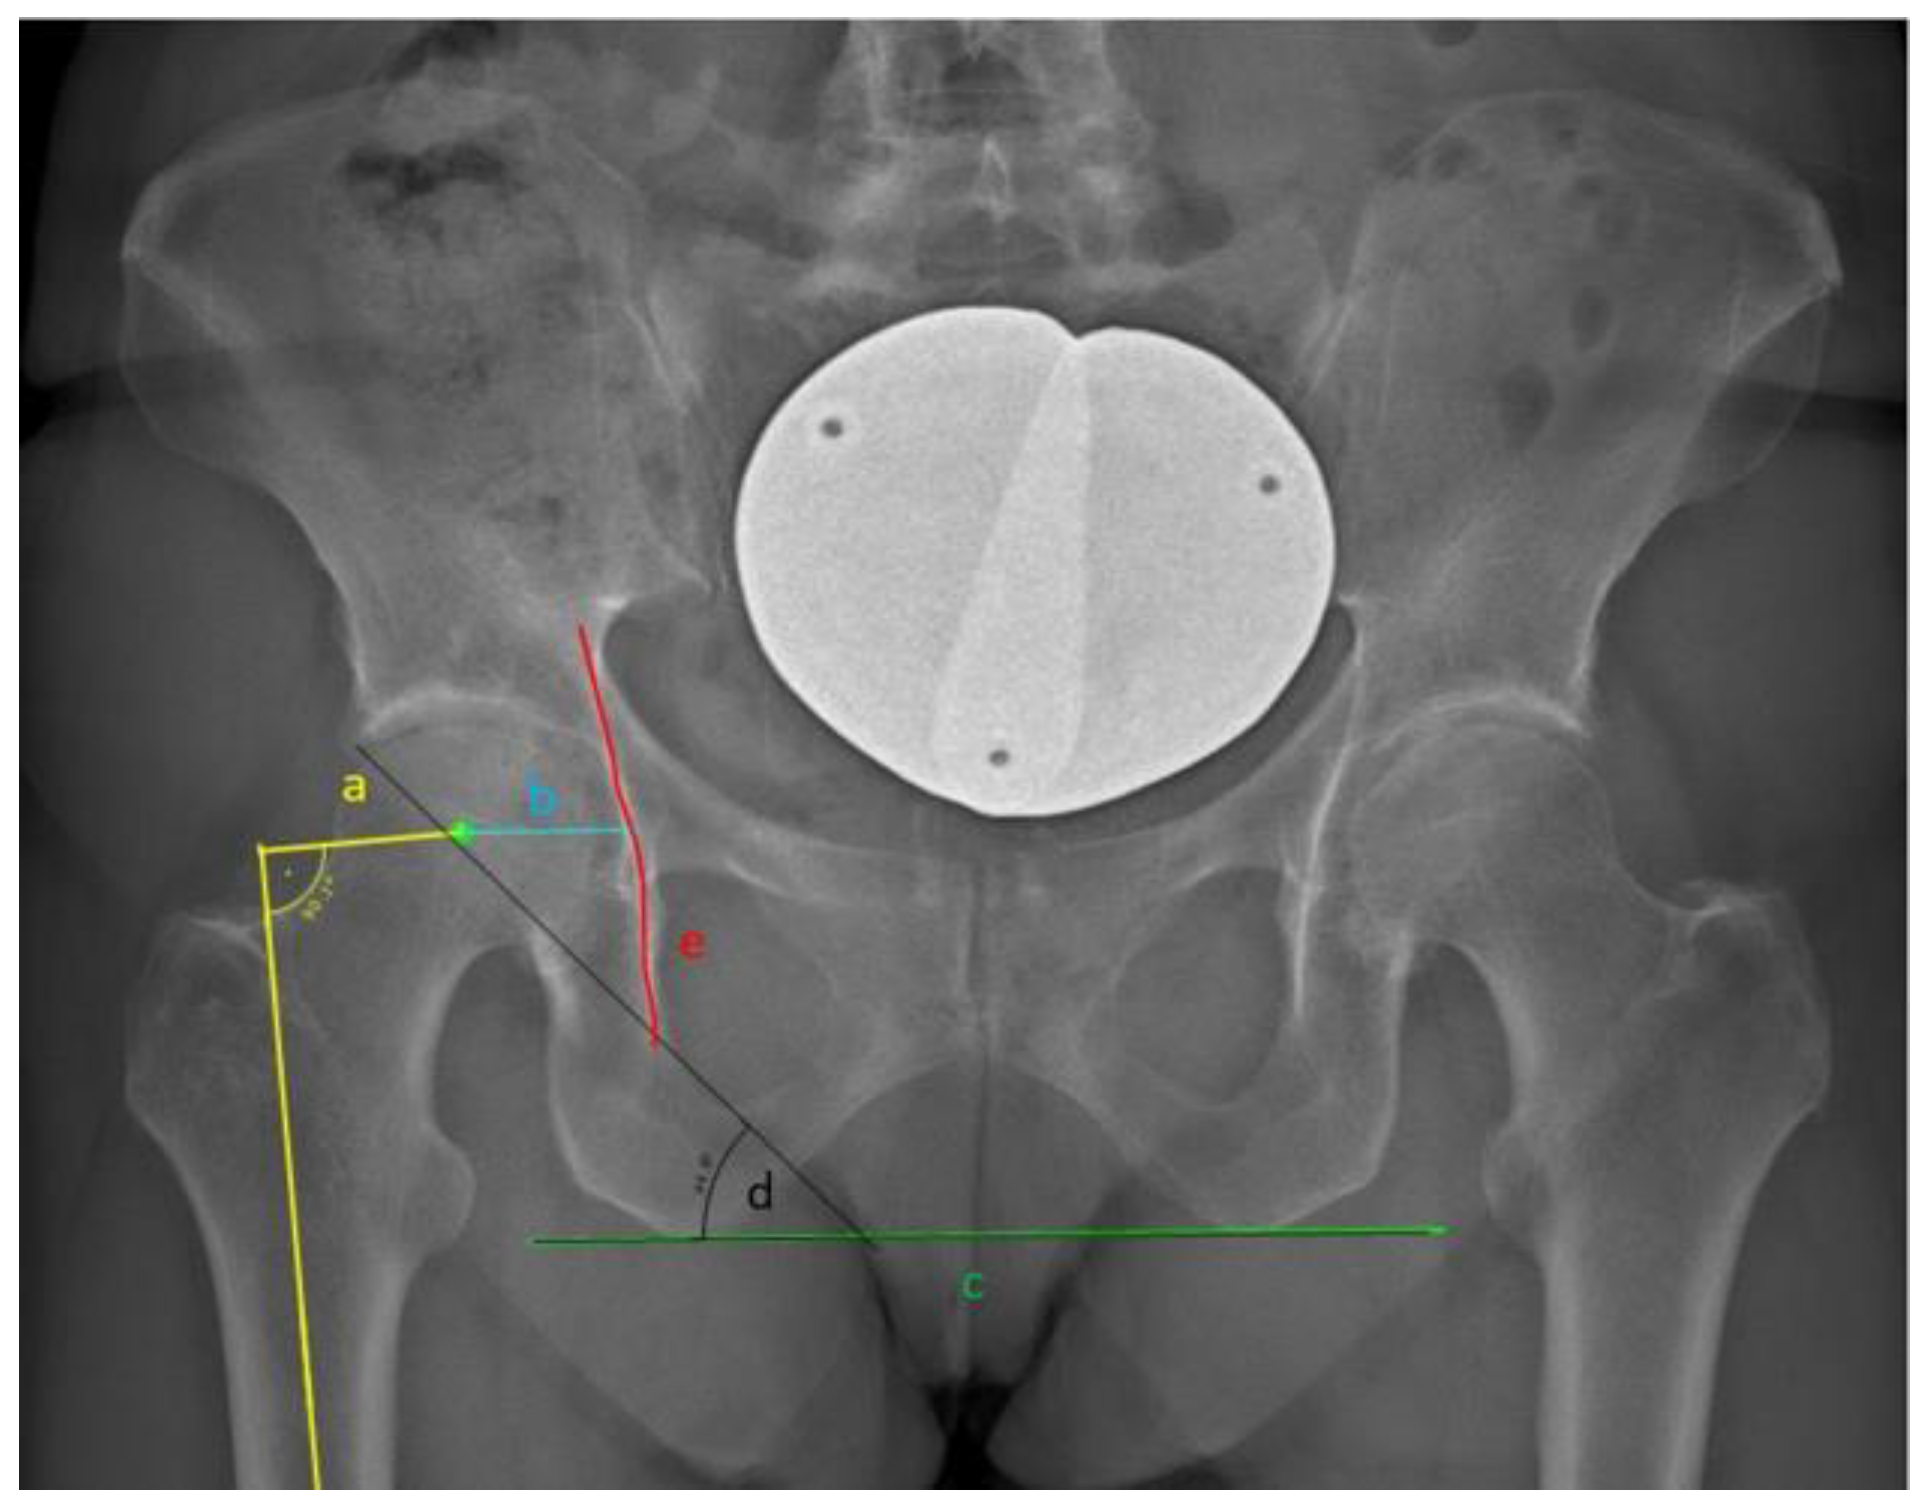

| Acetabular offset (mm) | AO: measured as the distance between the center of the femoral head and the ilioischial line (Figure 1). |

| Hip-Knee-Shaft-angle (°) | HKS: the frontal plane angle measured between the mechanical femoral axis and an axis running from the center of the trochlea to the center of the distal diaphysis. |

| Neck-Shaft-Angle (°) | NSA: the angle measured between the femoral diaphyseal axis and the axis going from the center of the femoral head through the femoral neck. |

| Hip-Knee-Angle (°) | HKA: represents the varus/valgus configuration of the knee. The HKA was defined as the angle in the frontal femoral plane between the mechanical axes of the femur and the tibia (the line from the center of the tibial plateau to the center of the distal articular surface of the tibia). A value greater than 0 ° equals a valgus alignment, and a value smaller than 0 ° equals a varus alignment. |

| Prosthesis stem-femur diaphysis angle (°) | angle between the anatomical femoral shaft axis and the longitudinal axis of the prosthesis stem. The anatomical femoral shaft axis was determined by connecting the centers of the two shaft diameters. The prosthesis stem axis was determined depending on the type of prosthesis. For the straight-stem prosthesis, the prosthesis axis was determined by connecting the proximal and distal points of the prosthesis (Figure 2a). For the short-stem, the axis was defined as the line connecting the distal end of the prosthesis and the lateral proximal shoulder of the prosthesis (Figure 2b). |